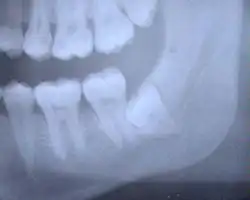

Als erster bleibender Zahn bricht der erste Molar (6er) ungefähr im Alter von sechs Jahren hinter dem letzten Milchzahn durch (also ohne dass ein Milchzahn vorher ausfällt). Man nennt ihn daher auch Sechsjahrmolar. Der zweite Molar (7er) bricht etwa im Alter von zwölf Jahren als vorläufig letzter durch. Der dritte Molar erscheint normalerweise erst im Erwachsenenalter (mit ca. 18 bis 25 Jahren) und wird deshalb auch Weisheitszahn genannt. Bei ca. 50 % der Menschen sind die Weisheitszähne nicht angelegt bzw. verlagert und/oder retiniert.

Im Unterkiefer haben die Molaren zwei Wurzeln. Davon liegt eine Wurzel mesial (vorne) und eine Wurzel distal (hinten). Pro Wurzel findet sich mindestens ein Wurzelkanal. Die mesiale Wurzel hat jedoch in der Mehrzahl der Fälle zwei Kanäle – ein Kanal liegt vestibulär (auf der Wangenseite) und der andere lingual (auf der Zungenseite).

Die Wurzeln der Weisheitszähne können sowohl in ihrer Zahl (1 bis 5) als auch in ihrer Form (zum Beispiel verkümmert oder mit Widerhaken) extrem variabel sein, ebenso die Anzahl der Wurzelkanäle. Das kann bei Zahnextraktionen zu Problemen und bei Wurzelbehandlungen zu unlösbaren Problemen führen.